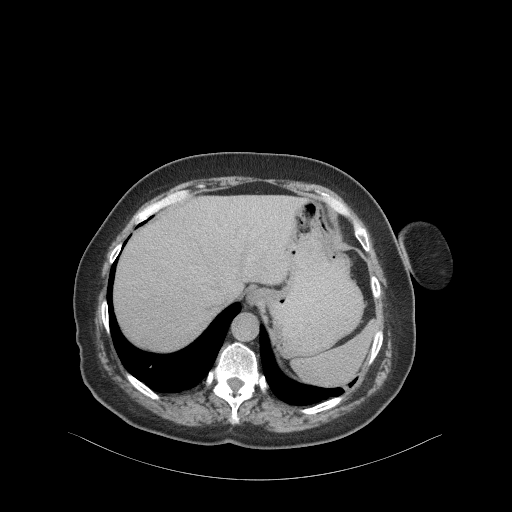

Original VENOUS CT scan

Full window (WL 1023.5, WW 4095 β†’ Low βˆ’1024, High +3071)

Actual HU range: [-160.0, 240.0]

Lung window (WL -600, WW 1500 β†’ Low βˆ’1350, High +150)

Actual HU range: [-160.0, 150.0]

Mediastinum window (WL 40, WW 400 β†’ Low βˆ’160, High +240)